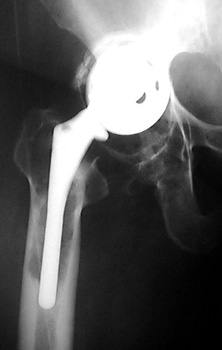

INFECTION—Markedly widened interfaces about acetabular and femoral components